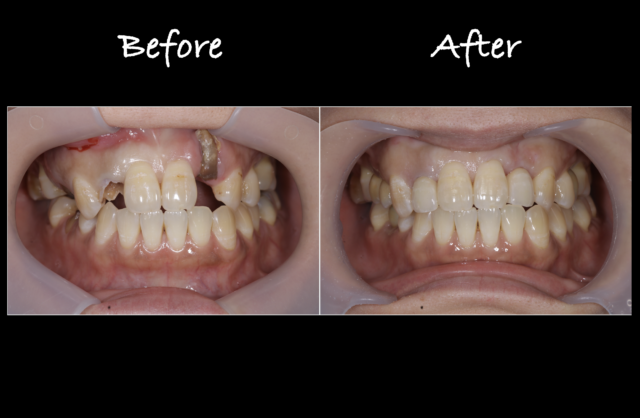

Before

After

術後口腔内

治療終了時。

審美的な状態を確保できている。